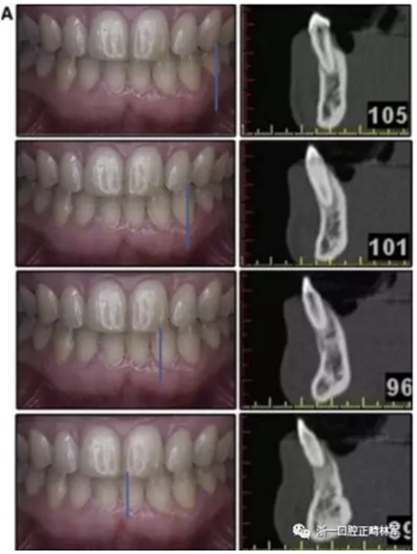

患者決定采用非手術(shù)治療方法,側(cè)貌沒有任何預(yù)期的變化。治療后面部照片(圖5)顯示她改善的微笑和側(cè)貌,包括尖牙保護合。由于先天性第一前磨牙缺失,右磨牙關(guān)系為III類。治療后牙齒石膏模型(圖6)顯示實體牙齒交錯排列情況,并且全景X線片顯示可接受的牙根平行度而且沒有牙根吸收表現(xiàn)(圖7)。最終的頭影測量片(圖7)證實了面部評估,并且描跡圖顯示深覆蓋的改善,同時保持上頜切牙位置并通過測量ANB角度和Wits評估改善骨性II級關(guān)系(表)。治療前后的疊加圖顯示由于下頜切牙前傾的增加改善了下唇平衡(圖8)。如相關(guān)治療計劃所預(yù)測的那樣,B點出現(xiàn)。A進行牙科錐形束計算機斷層掃描以記錄下頜前牙區(qū)的骨質(zhì)變化。如預(yù)期的那樣,由于治療導(dǎo)致該區(qū)域的骨量增加(圖9)。